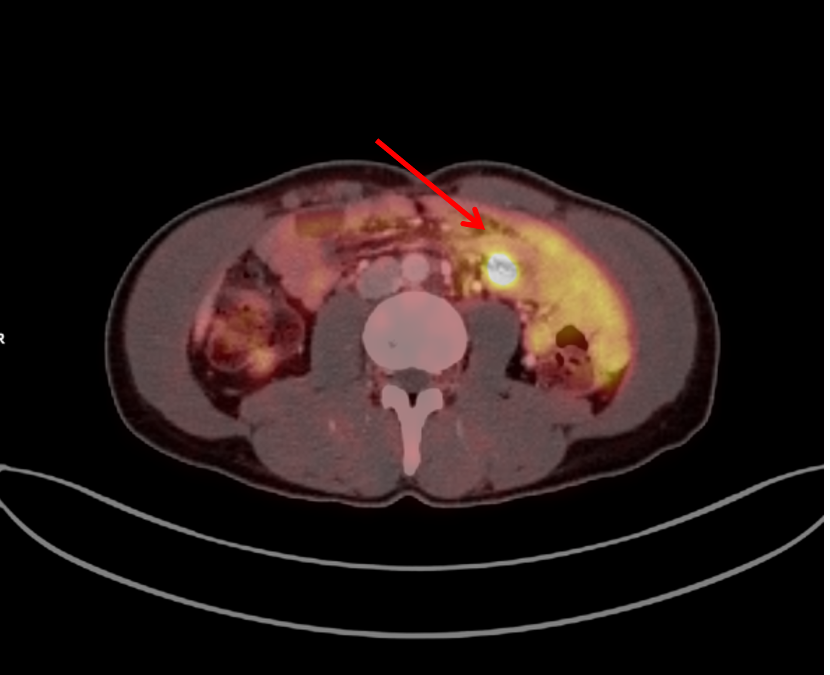

Metastatic ovarian cancer: 18F-FDG PET/CT imaging Fig. 1: Exemplary lymph node metastases Enlarged lymph nodes with high FDG uptake iliac (left arrow, SUVmax 8,2) and pelvic (middle / right arrow, SUVmax 11). Ileostomy in the right lower abdomen. Fig. 2: Peritoneal...